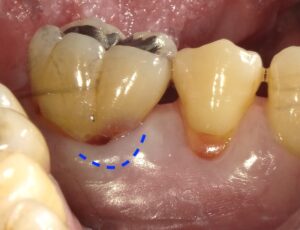

画像の様なイメージになります。針金を使いませんので

見た目がよくまた維持力も大きくとても良好な義歯となります。